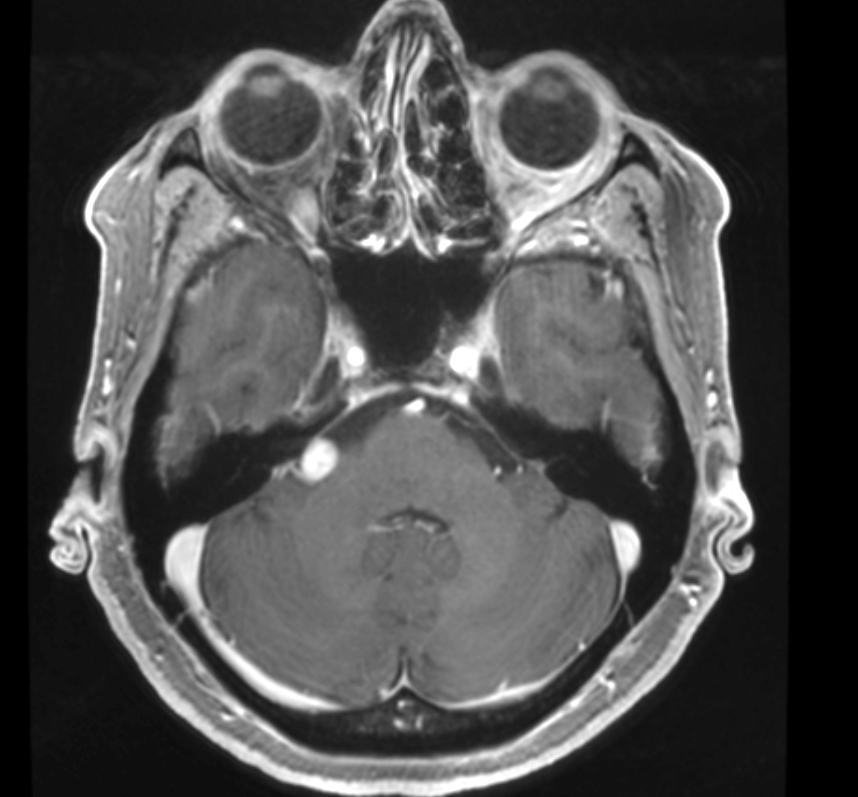

Radiology description

- Well circumscribed masses that displace adjacent structures without direct invasion

- On MRI, it may be

- Iso or hyperintense in T2 weighted images (Spine (Phila Pa 1976) 2017;42:E150)

- Hyperintense in fluid attenuated inversion recovery (FLAIR) images

- Heterogeneous or homogeneous enhancement in T1 weighted sequences (J Clin Imaging Sci 2017;7:38)

Radiology images